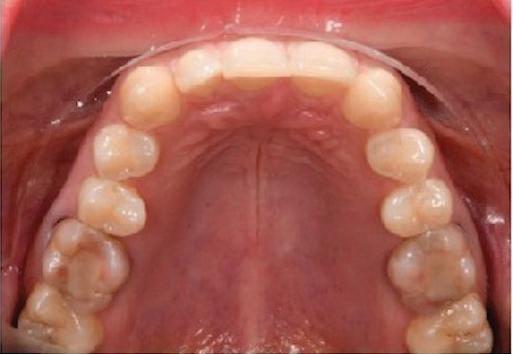

но

между членовете на екипа и пациента. ЗАКЛЮЧЕНИЕ Случаите на липсващи лате рални резци трябва да бъдат третирани от перспектива та на интердисциплинарна ди агностика и лечение. Употреба та на софтуера ClinCheck има доказани предимства за плани ране, комуникация между кли ницистите и пациента и фи нализиране на лечебния план, като се адресират всички же лания и притеснения на паци ента. Настоящият доклад на клиничен случай доказва, че с помощта на съвременните ме тоди един успешен екип от спе циалисти (ортодонт, консерва тивен зъболекар и хирург) може да се стреми към отлични ре зултати и да постига есте тични и функционални усмив ки без компромиси. Ред. бел.: Статията Treatment of a patient with a congenitally missing lateral incisor using aligners: A case report е пуб ликувана за първи път в сп. aligners–international magazine of aligner orthodontics, бр. 1, издание 1/2022. Библиографията е налична при издателя. За авторите: Д-р Iro Eleftheriadi завършва дентална медицина в Атинския университет, а магистратурата си по медицинска статистика – през 2014 г. в Публичния университет в Атина, Гърция. Специализира ортодонтия и завършва през 2017 г. в Университета в Тел Авив, Израел. Предстои ѝ да защити докторан тура във Факултета по дентална медицина към Университета в Атина, Гърция. Д-р Christodoulos Laspos завършва дентална медицина през 1995 г. в Атинския университет, Гърция, а магистратурата си завършва през 1999 г. във Фа култета по дентална медицина към Университета в Тенеси, Мемфис, САЩ. Печели стипендия и специализира лечение на пациенти с лицево-челюстни малформации в Университета в Тексас, Далас, САЩ, и е сертифициран специалист от Европейския борд на ортодонтите. Той е докторант в Универ ситета в Берн, Швейцария. От 2000 г. д-р Laspos практикува в частната си ортодонтска практика в Лимасол, Кипър. Той е основател и директор на MEDICLEFT, Кипърски център за цепки и лицево-челюстни аномалии, както и директор на фондацията Synergy, която осигурява следдипломно обучение на лекари по дентална медицина. Научен съ трудник е във Факултета по дентална медицина към Европейския университет в Кипър. Д-р Laspos изнася лекции по цял свят по теми като лицево-челюстни мал формации, ортогнатна хирургия, мултидисциплинарен подход и нови технологии в ортодонтията. Той е активен член на Европейското общество на Енгел и прези дент на Европейското ортодонтско общество. Фиг. 12а–c Финални странични (а и c) и фронтална интраорални снимки (b). Фиг. 13а и b Финални оклузални снимки. Фиг. 14 Финална снимка на усмивката отблизо. Фиг. 15 Финална екстраорална снимка на усмивката. Фиг. 16 Финална телерентгенография и цефалометричен анализ. Фиг. 12a Фиг. 13a Фиг. 14 Фиг. 15 Фиг. 16 Фиг. 13b Фиг. 12b Фиг. 12c клиничен случай с алайнери